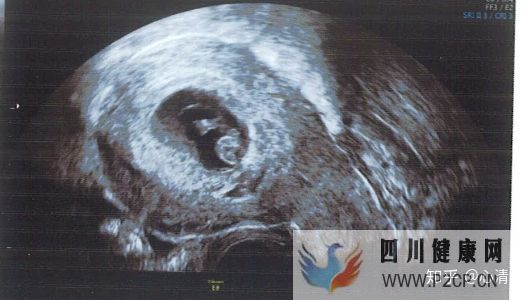

产检2020.3.30,孕12周+,做b超查NT值,一切正常,nt值1.5mm,低风险。

宝宝趴着呢,好可爱。2020.4.28,孕16周+,产检听胎心,145,做无创(唐筛的进阶版,检查染色体是否异常),抽血两次才成功,十多天后出结果,预约了22周的大排畸。不知何因转高危了,以后不能看普通号,只能看专家号。